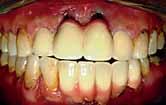

The patient had moderate Class II skeletal pattern with average Frankfort-mandibular planes angle and lower anterior face height. There was no facial asymmetry and the lips were incompetent with the lower lip trapped at rest behind the upper central incisors (Figure 1).

The oral hygiene was fair but needed improvement prior to orthodontic treatment. All teeth from the left permanent second molar to the right have erupted in both the upper and lower arches. The patient had carious lesions in both upper first molars, upper left second molar and lower left first molar. The maxillary arch was spaced with a midline diastema. Furthermore, there was mild lower labial segment crowding (4mm). The incisor relationship was Class II division 1, the overjet was 12 mm whereas the overbite was increased and complete to the palate

and causing trauma to the palatal mucosa. The centrelines were coincident and the buccal segment relationship was 1/2 unit Class II on both sides (Figure 2).